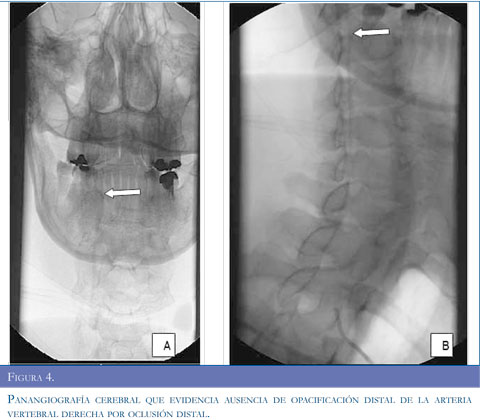

Con los argumentos descritos se realizó estudio de resonancia magnética del cerebro (Figuras 1 y 2) que evidenció infarto isquémico agudo del territorio de la arteria cerebelosa posteroinferior derecha (PICA), ecografía Doppler de vasos del cuello (Figura 3) que muestró aumento de las resistencias de las curvas obtenidas en la arteria vertebral derecha, con disminución significativa de su velocidad picosis-tólica y curvas con aspecto preoclusivo por lo cual se sospechó disección de la arteria vertebral. Se realizó panangiografía cerebral (Figura 4) que concluyó en disección de la arteria vertebral derecha con oclusión distal permitiendo aceptar la hipótesis planteada.